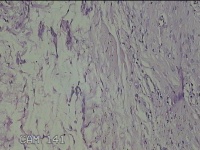

左大腿皮下结节

性别

女

年龄

30岁

临床诊断

皮下结节

一般病史

发现左大腿皮下结节1年余。

标本名称

大体所见

灰白粉红色组织1.7x0.8x0.3cm一个,表面带梭形皮肤 1.3x0.7cm,皮下见结节1.7x0.7cm一个,切开结节呈实性,切面灰白灰白粉红色,质中。

良性病变。